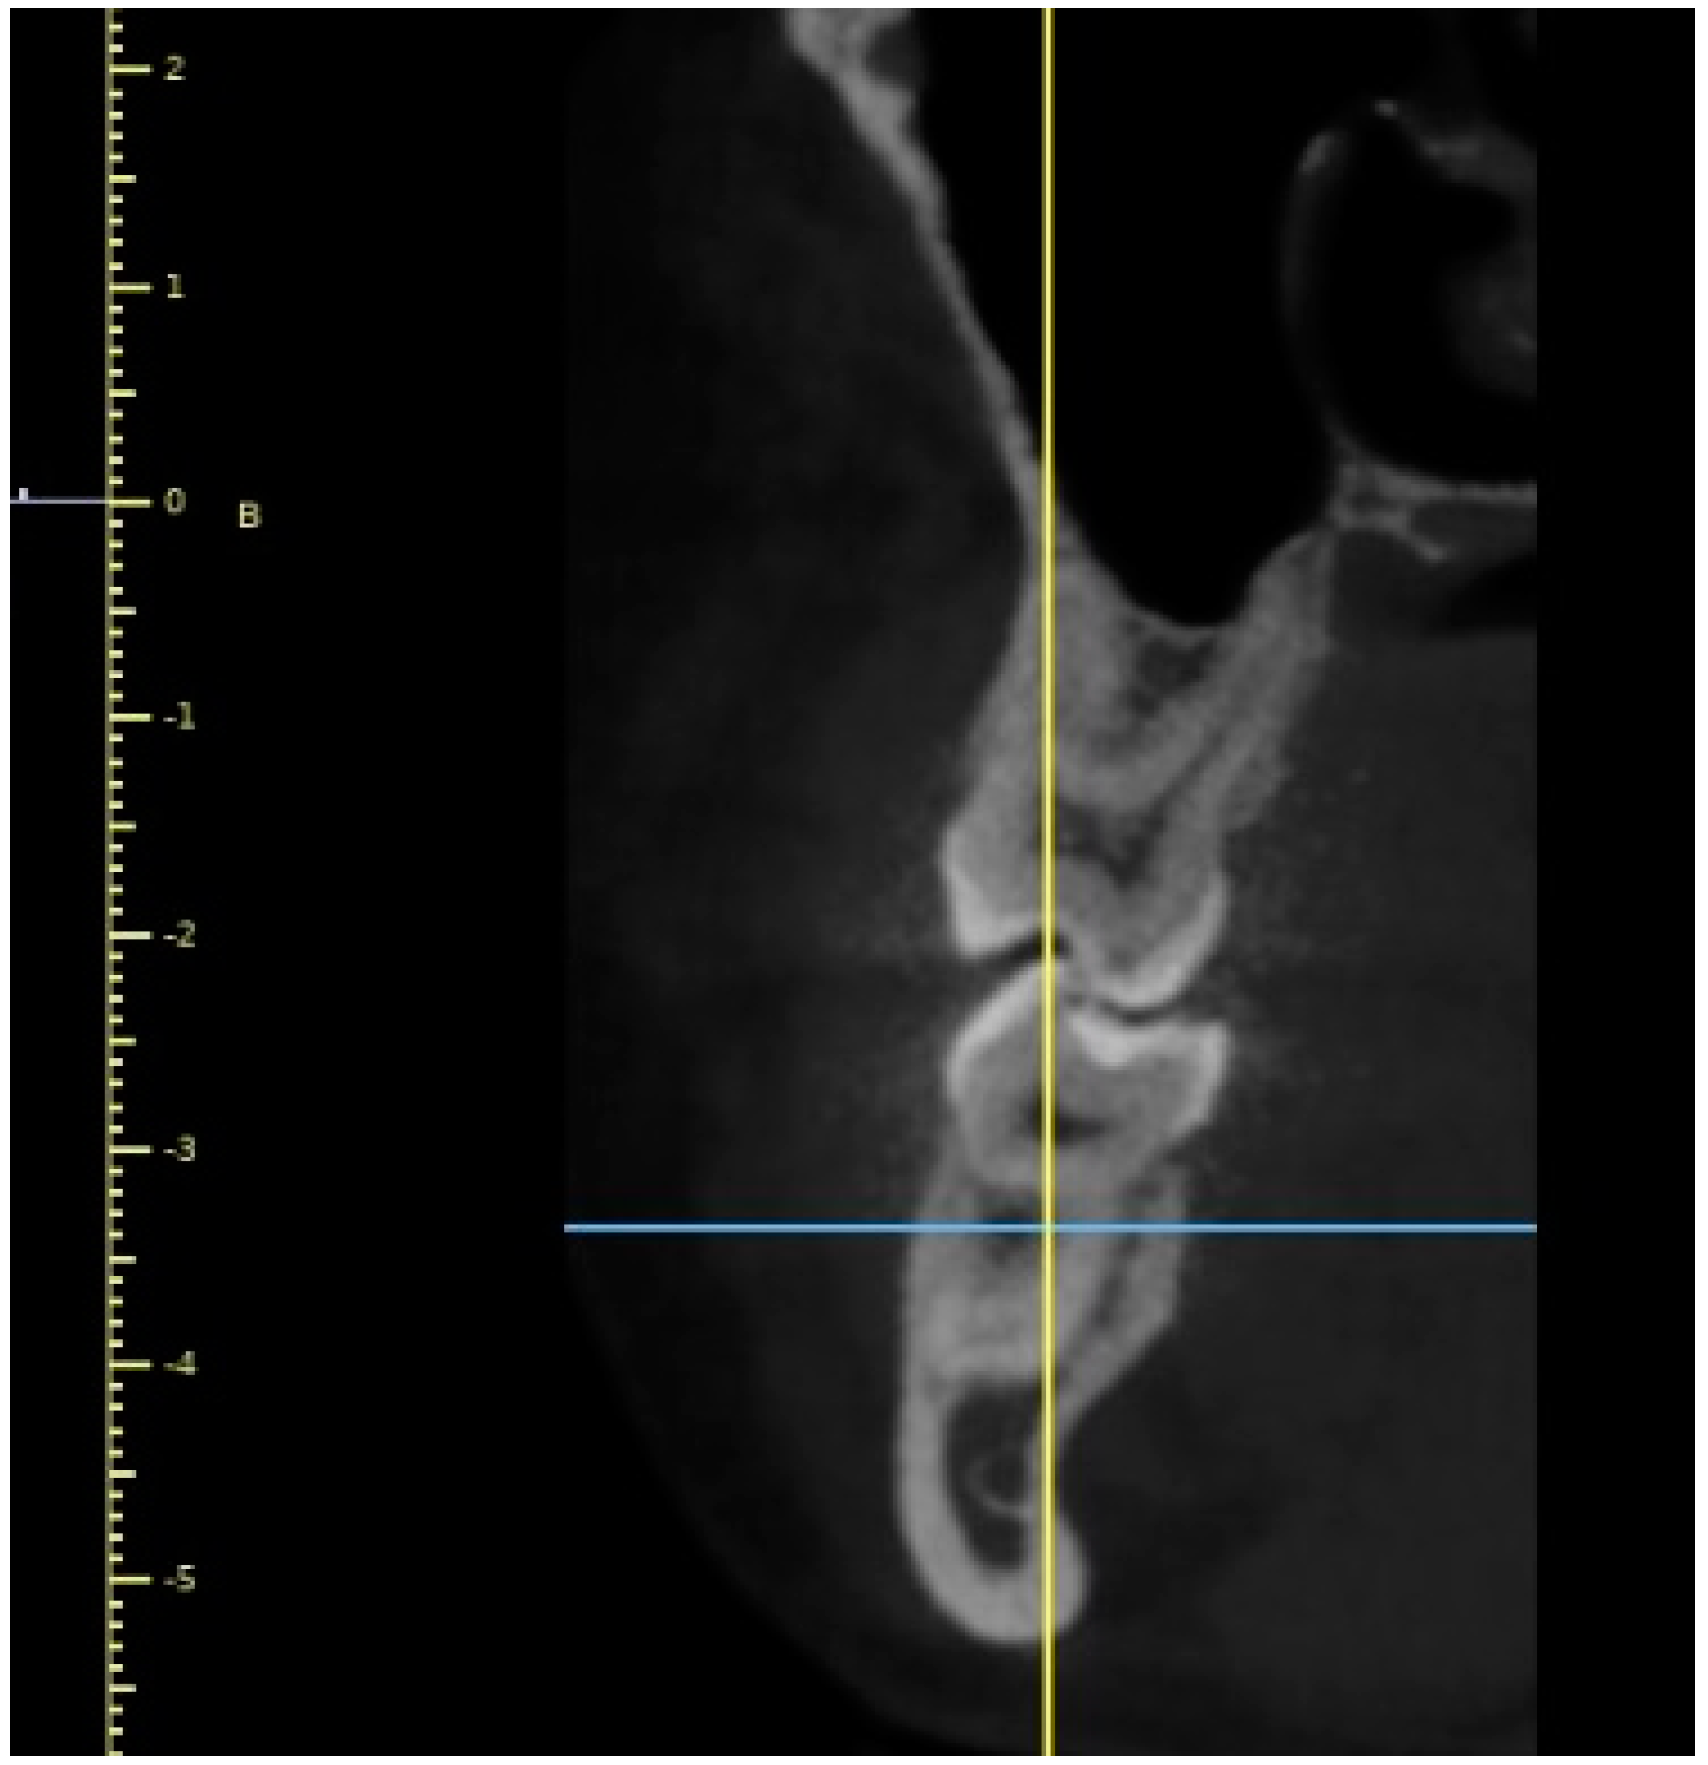

Initially, a panoramic image of patients was used for a general dental evaluation and select cases according to inclusion criteria as shown in Figure 2. An axial view of the maxillary arch was used to evaluate the number of roots and canals in maxillary molars as shown in Figure 3. Subsequently, the coronal view was used to evaluate the type of Vertucci’s classification in the palatal root of maxillary first molar as shown in Figure 4.

Figure 4.

Coronal view of maxillary right molar (#16) showing Vertucci’s Type-I canal configuration.